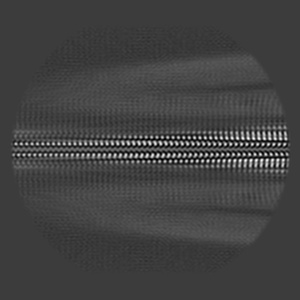

The L1 amyloid-beta(1-40)fibril in the presence of anle138b (pre-treatment)

Helical reconstruction2.76 Å

Sample: The L1 amyloid-beta(1-40)fibril in the presence of anle138b (pre-treatment)

Anle138b binds predominantly to the central cavity in lipidic A beta 40 fibrils and modulates fibril formation.